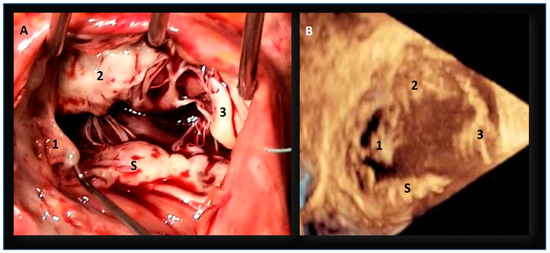

- Which is the best noninvasive imaging technique to visualize TV?

- How many leaflets has the valve?

6. How Many Leaflets Has the Valve?

7. What Are the Similarities and Differences between the Tricuspid and Mitral Valve